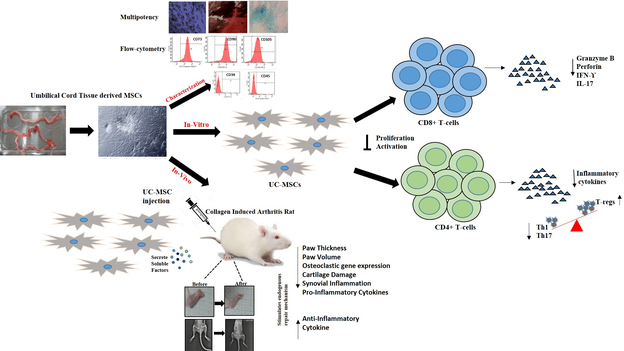

Human umbilical cord derived mesenchymal stem cells induce tissue repair and regeneration in collagen-induced arthritis in rats

Translational research